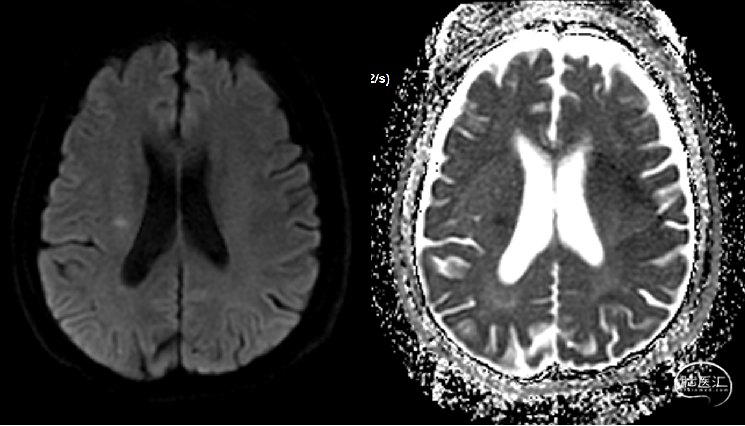

头颅核磁提示:右侧大脑半球、双侧小脑半球多发散在DWI高信号,考虑急性亚急性脑梗死;头颅MRA未发现明显重度狭窄及闭塞大血管。

急诊头颅MRA未见颅内大血管较重狭窄或闭塞。